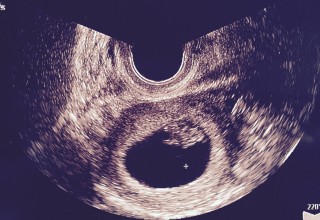

最初の受診から2週間後。期待と不安が半分半分の2週間でした。無事赤ちゃんと心拍確認できました。「元気に動いてますよ」と先生に言ってもらえました。一安心。また2週間後の受診も元気に成長していてほしいです。CRL11.1mm

一週間前6w5dで胎嚢の中身が空っぽでした。 半分諦めて受診した7w5dで心拍、卵黄のう、胎芽の全てが確認出来ました! のちの数週訂正でこの時8w3dとなります。 胎嚢の大きさ的には6w6dとなっています。